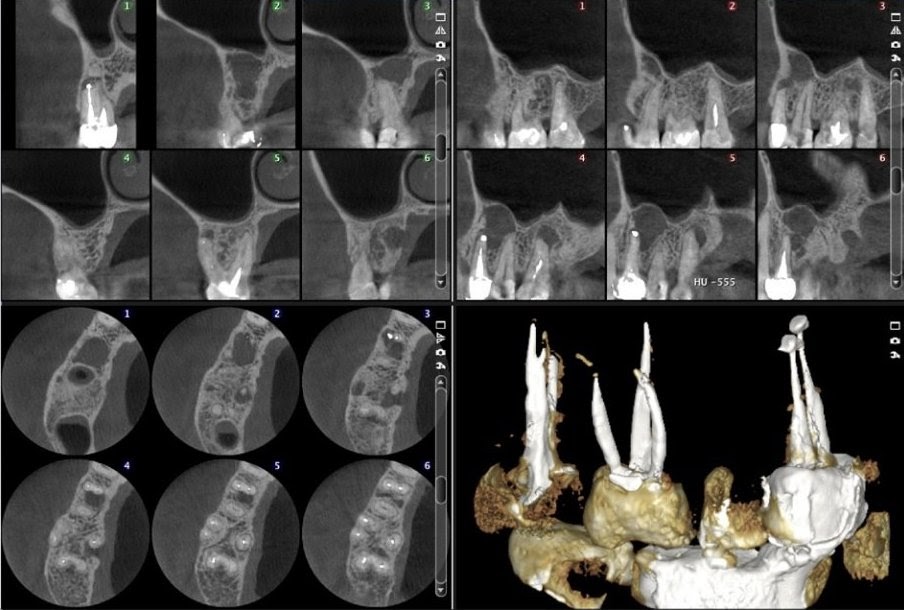

По снимкам дентального томографа терапевты смогут изучить направление нерва в каналах зуба, проверить количество каналов, найти застрявшие фрагменты инструментов, обследовать трещины, кисты и гранулемы на верхушке корня. У хирургов с 3D-снимками рабочей области будет четкая диагностическая картина для сложного удаления, в том числе ретинированных третьих моляров. Также без объемной картинки сложно предсказать результат работы с кистоподобными образованиями, травмами и опухолями зубочелюстной системы.

Снимок ортопантомографа очень информативен, но не показывает объем и качество костной ткани, не отражает реального состояния корней. К сожалению, за тенями корней зубов часто скрываются патологические изменения, а они в разы увеличивают риск послеоперационных осложнений. Ориентируясь только на двухмерный снимок, можно пропустить очаг инфекции в зоне имплантации, задеть нерв или крупный, аномально расположенный сосуд.

Имплантологу стоматологический томограф дает точные данные для позиционирования имплантата, включая ширину, высоту, плотность и качество костной структуры. Что, в свою очередь, позволяет выбрать правильный протокол и правильный имплантат.

В челюстно-лицевой хирургии только томограф позволит детально оценить локализацию, границы и распространенность патологического процесса челюстных костей или гайморовых пазух, определиться с объемом оперативных вмешательств и оценить результаты лечения.

Как выбрать томограф в стоматологию